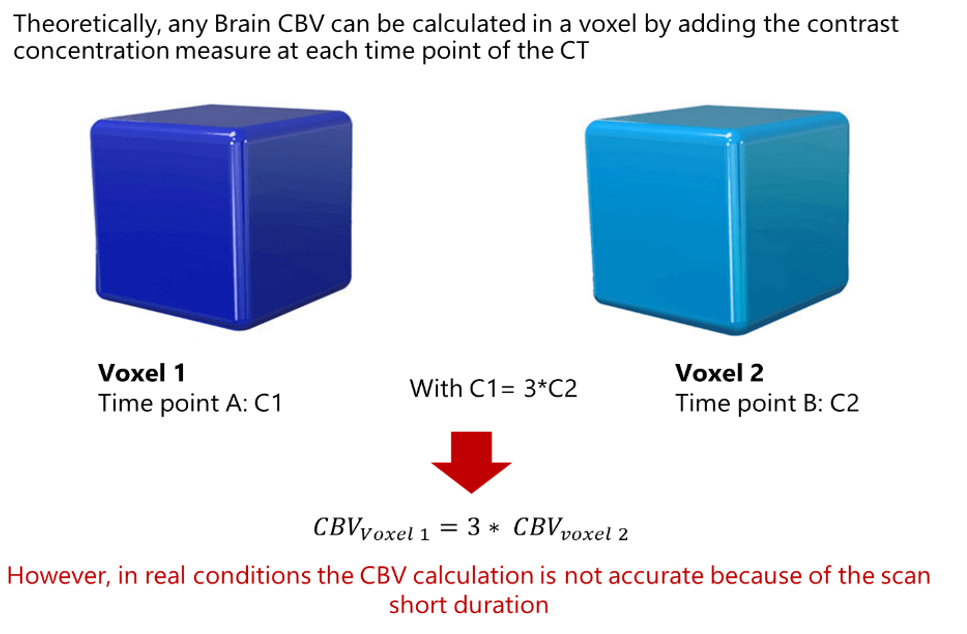

The Cerebral Blood Volume CBV, is defined as the volume occupied by intravascular blood in any particular section of brain tissue. It is measured in units of milliliters of blood per 100 g of brain.

Theoretically, any Brain CBV can be calculated in a voxel by adding the contrast concentration measure at each time point of the CT. Thus, if the concentration at time point A in a particular voxel is triple that of time point B in a second voxel, the CBV in voxel 1 is 3 times greater than in voxel 2. However, in real conditions the CBV calculation is not accurate because of the scan short duration.

We have mentioned earlier that the CBV calculation is not accurate because of the scan short duration. This is right because a typical perfusion CT requires a contrast injection time of about 10 seconds, followed by only 35 seconds for the bolus to pass from the arm to the brain.

Besides, it is known that some portions of the bolus take a much longer time to reach the brain, thus causing errors in CBV estimation.

An additional cause of error involves the phenomenon of recirculation, which can occur in short-duration scans. Indeed, multiple recirculation passing through the brain may take place during a single perfusion scan, as the initial recirculation of the bolus starts prior to completion of the initial pass. As a consequence, the CBV of any particular voxel may actually measure the summation of multiple passes, overestimating the contrast concentration at that time point.

Underestimation of the tissue concentration can also occur, if the arrival of the bolus is slowed through any or several parts of the brain. Post-processing software, which applies algorithms that overcome the recirculation phenomenon, allows the calculation of regional CBV by integrating the contrast concentration at each of the time points (Ct) over the duration of the scan. Through this approach, scans of longer duration can generate reasonably accurate CBV measurements.